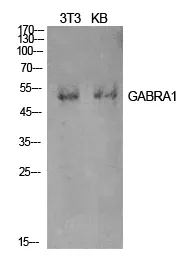

GABAA Rα1 Rabbit Polyclonal Antibody

Cat: APRab11233

Size1:50μl Price1:$118

Size2:100μl Price2:$220

Size3:500μl Price3:$980

Size2:100μl Price2:$220

Size3:500μl Price3:$980